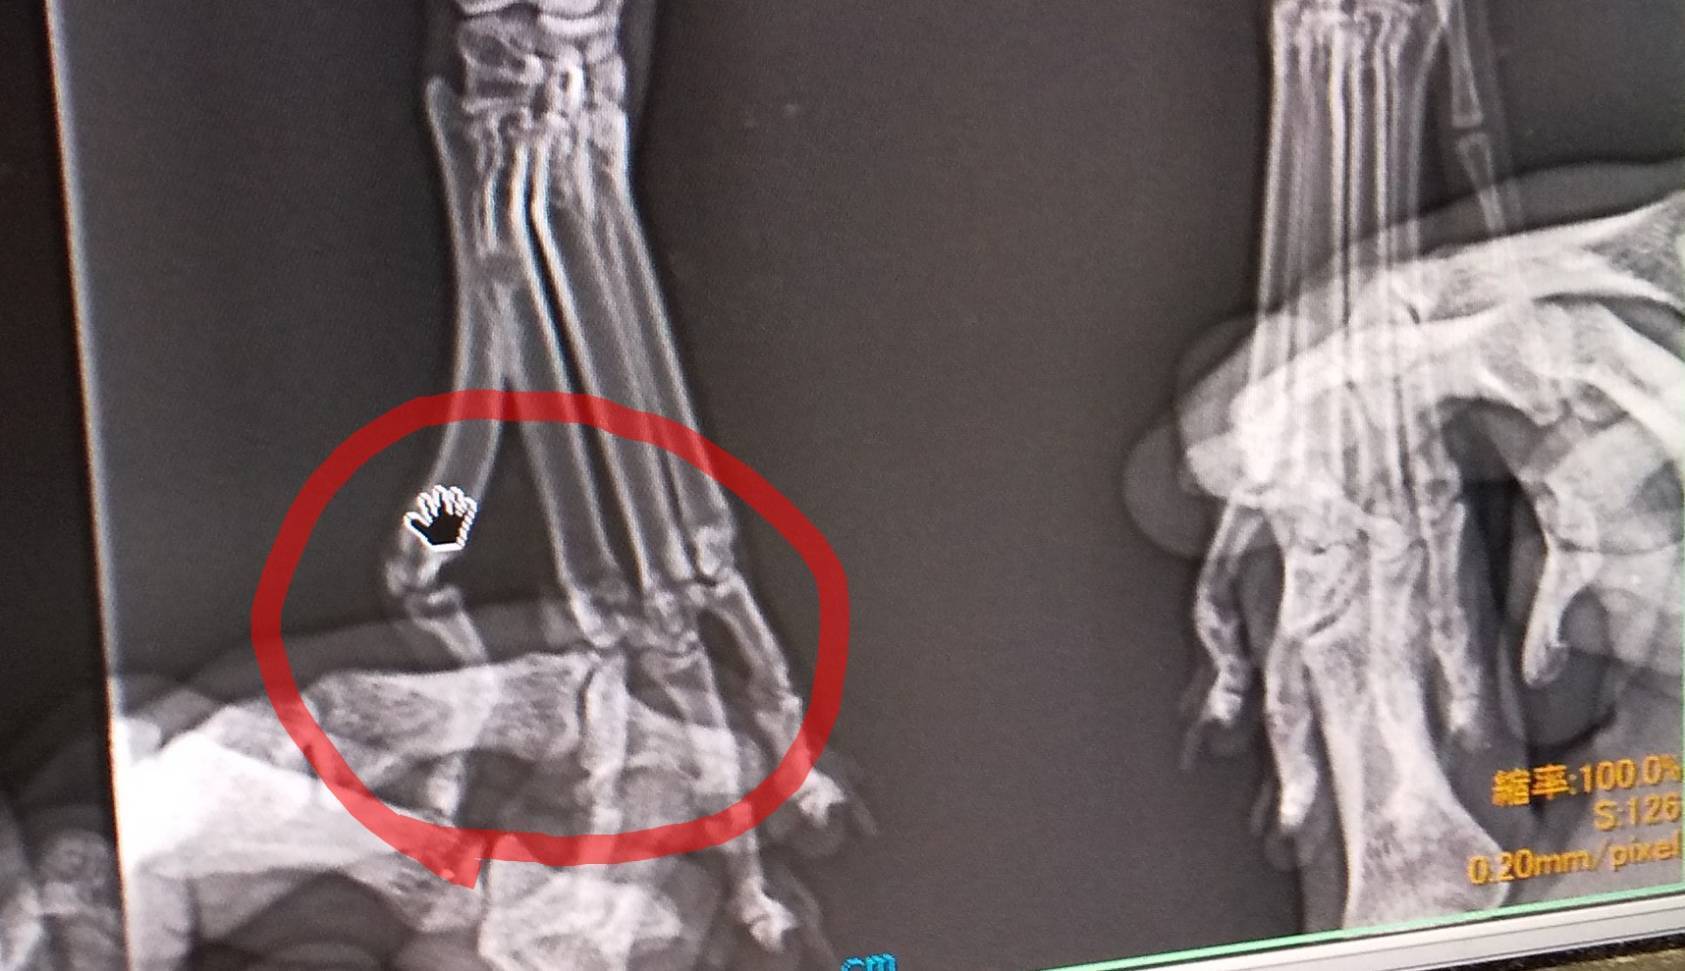

レントゲン②

骨折2ヶ所目。

こちらは手術せずに治せるそうです。